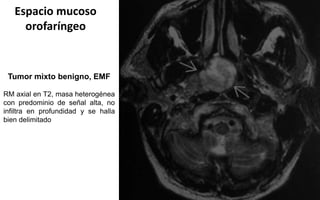

Tumor mixto benigno, EMF

RM axial en T2, masa heterogénea

con predominio de señal alta, no

infiltra en profundidad y se halla

bien delimitado